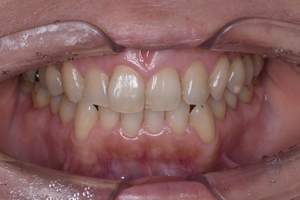

全顎SCとPMTC

治療前

治療後

| 年齢 | 33歳・男性 |

| 主訴 | 全顎SCとPMTC |

| 治療内容 | SC、PMTC (自費診療) |

| 治療期間 | 60分 |

| 費用 | SC 5,500円(自費診療) PMTC 5,500円 (自費診療) 合計 11,000円 (2024年1月現在) |

| リスク・副作用 | ・処置後に歯がしみることがあります ・歯と歯の間に隙間ができるので、息が漏れ発音しにくいと感じることがあります ・歯ぐきの炎症が軽減すると歯ぐきが引き締まり、歯が長く見えることがあります ・PMTCは歯を白くするものではなく着色·バイオフィルムの除去を目的としています。 ・PMTCは保険適用外の施術です。 |

| 治療方針 | 前歯の裏の着色が気になるとの事で来院されました。 虫歯治療は他院でおこなっているため、着色を落として欲しいとのご希望でした。 口腔内写真をお見せてして、着色と歯石も着いていることを説明しました。 歯石除去と歯の表面に付着したプラーク、着色を取り除きました。 また、セルフケア指導も行いました。 |

| 担当者所見 | 歯石がなくなり、PMTCでつるつるになったと喜んでいました。 ご自身でしっかり歯磨きが出来るように1本ずつ丁寧に磨くことをお話しさせて頂きました。 柔らかめの歯ブラシで斜め45度に歯と歯ぐきの境目に当て磨くレッスンを行いました。 今後も定期的なメインテナンスを行っていく予定です。 |